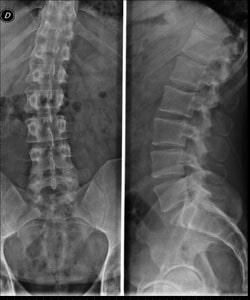

Como médico traumatólogo se especializa en cirugía de columna vertebral, y ofrece los mejores cuidados ante deformidades, escoliosis, pie plano, hernias de disco, fracturas y otros problemas en esa área.

- Escoliosis

- Columna desviada